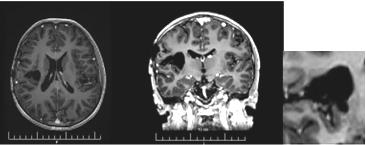

A 57-year-old man with non-small cell lung cancer NSCLC/ adenocarcinoma is presented. Due to complaints of headache, nausea and vomiting after CT, two brain metastases were proven in the right brain hemisphere with frontal and parietal parasagital localization. The right frontal metastasis with dimensions 32mm/ 30mm was surgically removed. Postoperatively, intensitymodulated WBRT with DD 2.5 Gy up to TD 27.5 Gy with boost in the right parietal parasagital metastasis up to OOD 33 Gy with DOD 3 Gy / total radiobiologically equivalent dose (BED) 60 Gy was carried out (Figure 8). After 4 months, in another medical institution, despite the lack of cerebral symptoms, local RT by the VMAT method in the area of same metastasis up to TD 20 Gy with DD 4 Gy was performed. After 7 months of the second RT, of CT with venous contrast, a parasagittal cystic lesion up to 14 mm in size in the right parietal supratentorial area was visualized, most likely a necrotic brain tissue with pronounced frontoparietal edema (Figure 9).

Figure 7: CT of the second local recurrence: A / before the local RT; B / Over 50% reduction of tumor volume after local RT up to TD 45 Gy with DD 1.8 Gy.

Figure 8: The intensity modulated WBRT with DD 2.5 Gy up to TD 27.5 Gy with boost in the postoperative metastatic bed up to OOD 33 Gy with DOD 3 Gy.

Figure 9: CT of the brain - A parasagittal cystic lesion up to 14 mm in size in the right parietal supratentorial area with frontoparietal edema, most likely a necrotic brain tissue.

Although different fractionation schedules of WBRT do not influence survival [32], it appears that escalating the dose to the metastatic lesions increases intracerebral control as well as OS, compared to WBRT alone [53,54]. WBRT with 3D conformal boost is a feasible technique which improves the quality of life (QOL) of patients with a reduced number of brain metastases, regardless of the fractionation regimen or the total dose administered to the metastatic lesions [34]. In the third clinical case, with NSCLC after WBRT with VMAT boost in the brain metastasis to cumulative biological equivalent dose (BED) 60 Gy (Figure 8), a second hypofractionated Intensity modulated Re-irradiation with DD 4 Gy up to TD 20 Gy was conducted. Late side effects appear after 6 months of RT or later include visible radionecrosis of the brain with fields of focal coagulation necrosis and progressive microvascular occlusion with increased risk of stroke [55-58]. Data exist concerning the re-irradiation of brain tumors to a median cumulative BED (biological equivalent dose in 2Gy fractions) of 200Gy, with at least one year between the two treatments. Longterm complications related to the retreatment were seen in patients with a BED2>204Gy (α: β=2 Gy) [59]. Although the BED does not exceed 200 Gy, the radionecrosis of the clinical case is due to the short time (less than 6 months) between the retreatment as well as the high daily dose of 4 Gy (Figure 9).